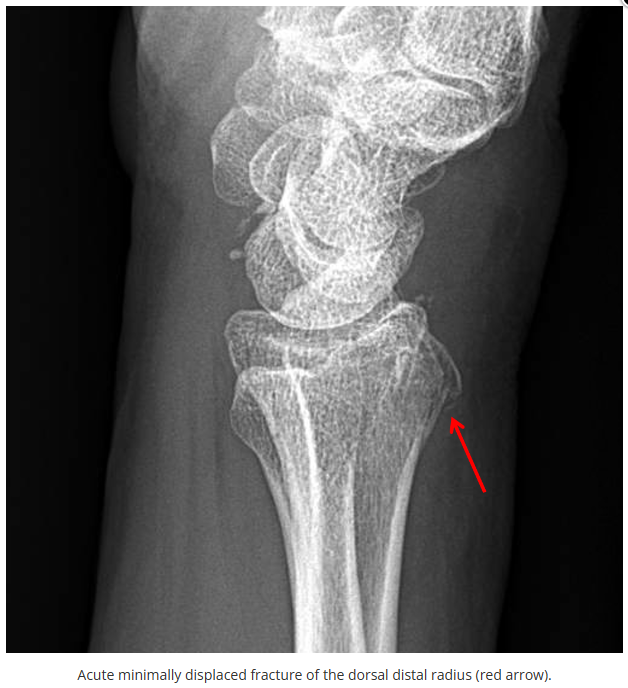

这些腕与手的骨折X线片如果没有标注箭头,你还能识别出来吗?

X线读片是骨科医生的基本功。

今天是腕部与手的X线片。所有X线片都

带有标注和说明

,可以选择长按图片,

自动翻译相关说明

。